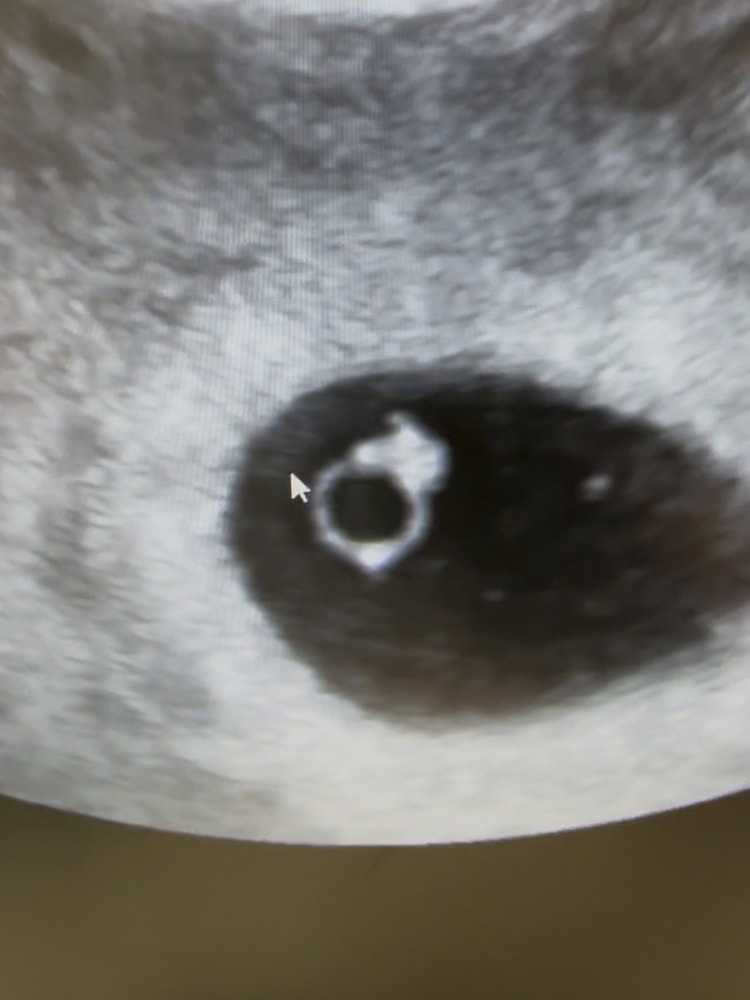

13.10 узи: плодное яйцо 9мм, желточный мешочек

18.10 узи: эмбриончик 3,5 мм, пульсация сердечка.

срок на 18.10 6.5 недель по месячным. Но по узи меньше, цикл длинный,овуляция поздняя. Назначили поддержку дюфастоном, витамины разные прописали, надеюсь поможет все это вместе эмбриончику догнать срок🙏